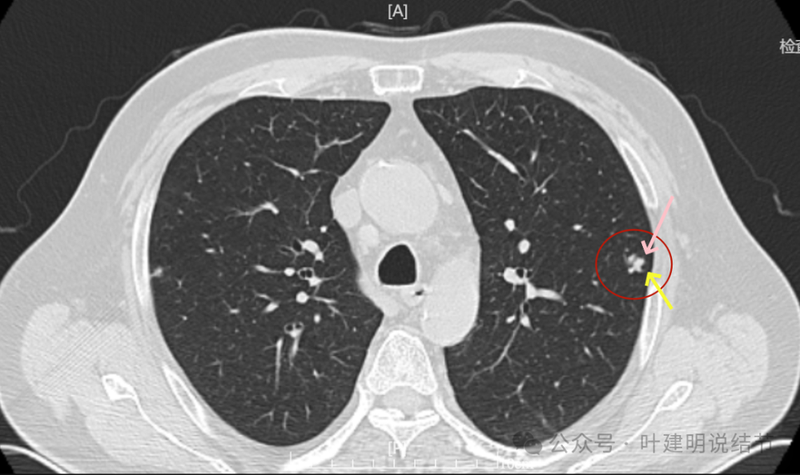

局部放大病灶表面不平,血管进入,进入的血管有异常增粗,没有见到明显卫星病灶。

明显实性成分,灶边的细支气管有扩张。

血管与之关系密切,实性密度。

整体有膨胀感,血管有进入病灶。

血管进入明显,边缘毛糙不光滑。